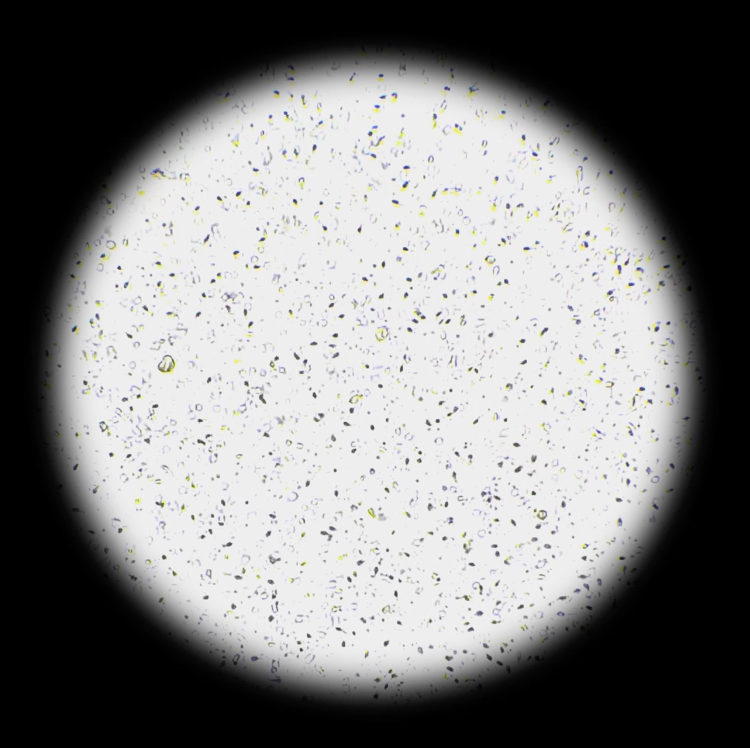

[NEW] 하고보고 정자 관찰기 2세트

집에서 간편하고 신속한 정자 상태 확인!